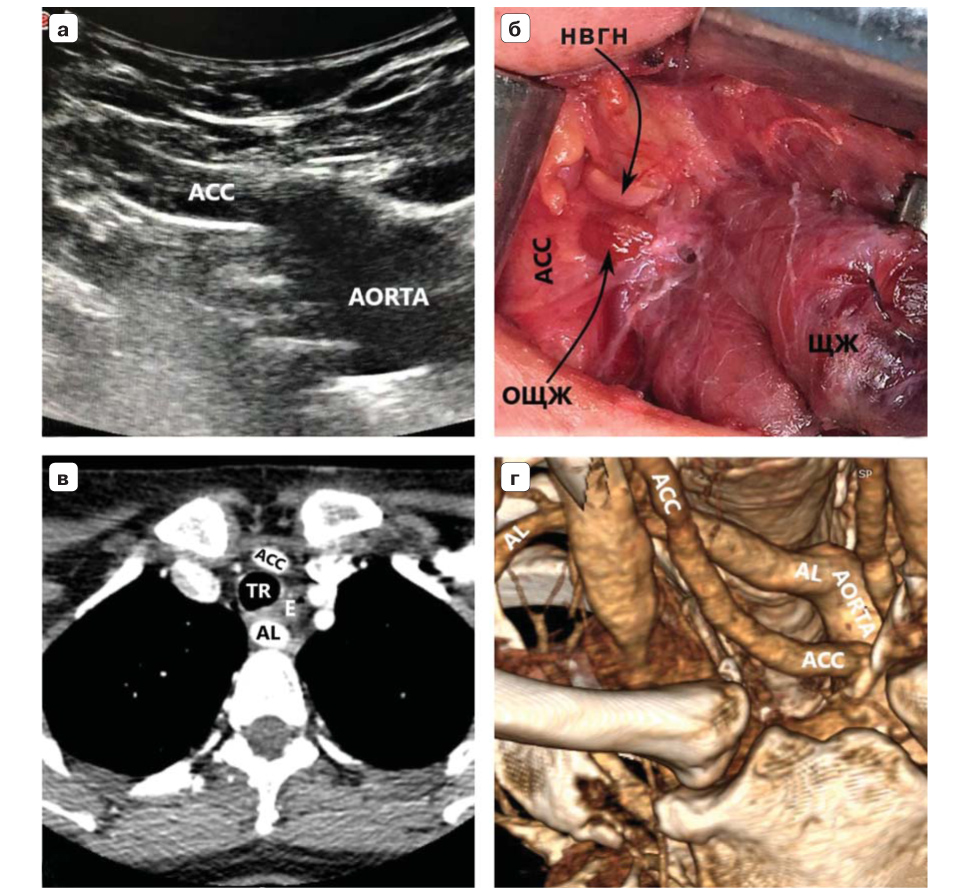

16. Fig. 5. The patient is 62 years old, BMI is 51.4. a - ultrasound of the vascular bundle of the right half of the neck with a convex sensor. AL “leaves” due to the trachea and is located almost horizontally, high on the border of the neck and upper mediastinum. b - intraoperative picture. Type IIA NVGN (according to Avisse – Toniato) has a horizontal course. c - axial CT scan with angiography of the vessels of the aortic arch. AL is located behind the trachea and esophagus. g - computer three-dimensional reconstruction (rear view). AL is the last, fourth branch of the aortic arch. ACC - arteria carotis communis (A - dexter, D - sinister), TR - trachea, E - esophagus. VJI - vena jugularis interna dexter, AS - arteria subclavia sinister. | |

2. Fig. 2. The patient is 32 years old, body mass index (BMI) - 18.5. a - ultrasound of the vessels of the upper mediastinum with a convex sensor in B-mode (color duplex scanning is less informative due to a lot of interference from the aortic arch). The right common carotid artery was traced to the aortic arch (BCC was not detected). b - intraoperative picture. Type IIA NVGN (according to Avisse – Toniato) has a horizontal course. c - axial CT scan with angiography of the vessels of the aortic arch. AL is located behind the trachea and esophagus. d - computer three-dimensional reconstruction demonstrates AL syntopia with a common carotid artery. AL is the last, fourth branch of the aortic arch. ACC - arteria carotis communis dexter, TR - trachea, E - esophagus. | |